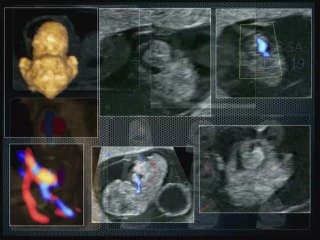

La plus grande ressource vidéo en échographie fœtale de France. Conférences, cours magistraux, démonstrations pratiques et podcasts par les experts du Collège Français d'Échographie Fœtale.

La médiathèque du Collège Français d'Échographie Fœtale (CFEF) constitue l'une des plus importantes collections de ressources vidéo dédiées à l'échographie fœtale en France. Avec plus de 3 261 vidéos, elle couvre l'ensemble des thématiques liées à la pratique échographique prénatale.

Vous y trouverez des conférences présentées lors des congrès nationaux et internationaux, des cours magistraux dispensés par des experts reconnus, des démonstrations pratiques sur des cas cliniques réels, ainsi que des podcasts et tables rondes sur les dernières avancées de la spécialité.